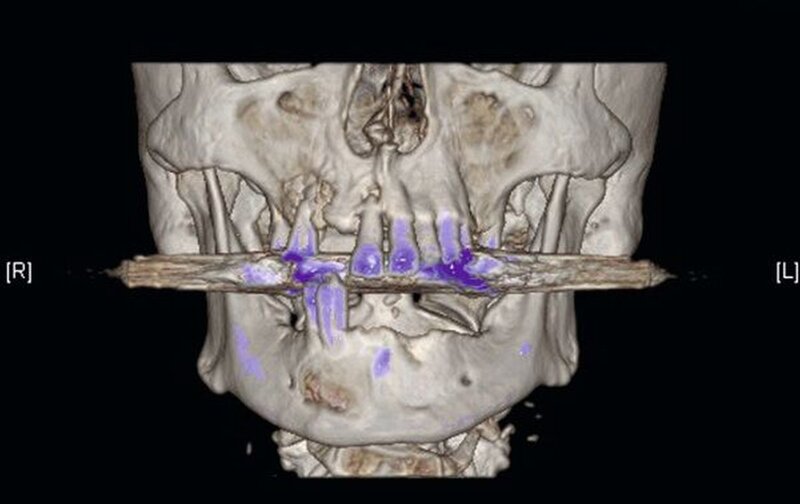

Die Computertomografie der Nasennebenhöhlen (NNH-CT) (nativ) zeigte dann das Ausmaß der knöchernen Destruktion. Neben der ausgedehnten generalisierten Nekrose des Oberkiefers konnte nebenbefundlich eine zystische Läsion im Bereich des Unterkiefers Regio 41 bis 45 diagnostiziert werden. Voraussichtlich ging diese vom Wurzelrest des Zahnes 41 aus. Weiterhin bestand eine totale Verschattung beider Sinus maxillaris und eine akzentuierte Lymphadenopathie in allen abgebildeten Leveln.